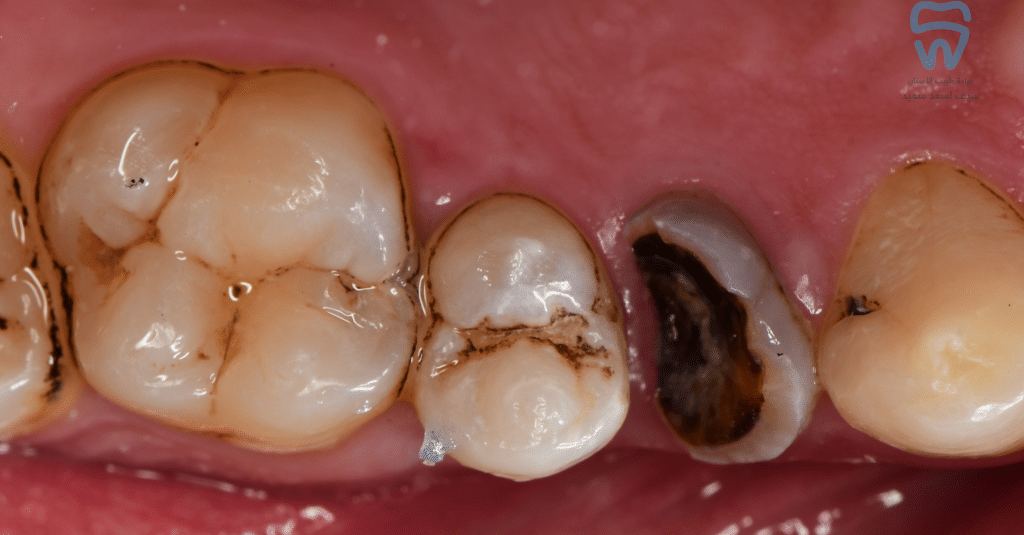

Buccal view of the cavities

Margin build-up

finished layering of composite

After polishing and high spot adjustment